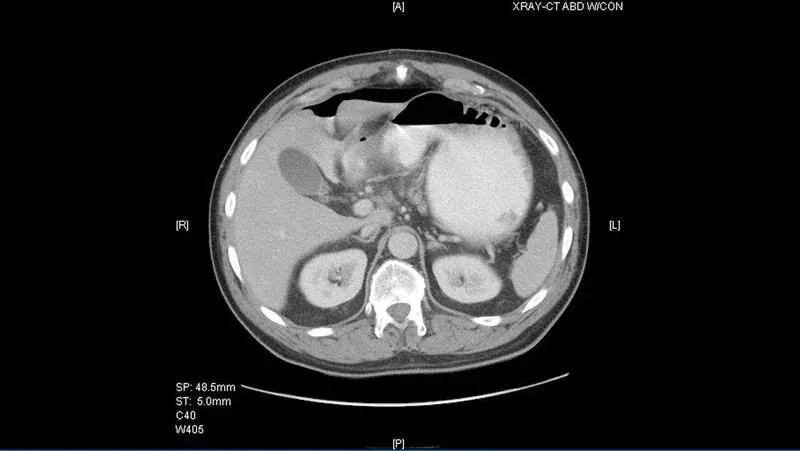

初始检查完成后,给患者注射额外剂量的静脉止痛药,可明显缓解部分疼痛(尽管上腹部的局部疼痛仍持续存在)。患者稍后做了腹部和骨盆的 CT 检查,并获得口腔和静脉造影图像(图 1 和图 2)。

图 1

图 2